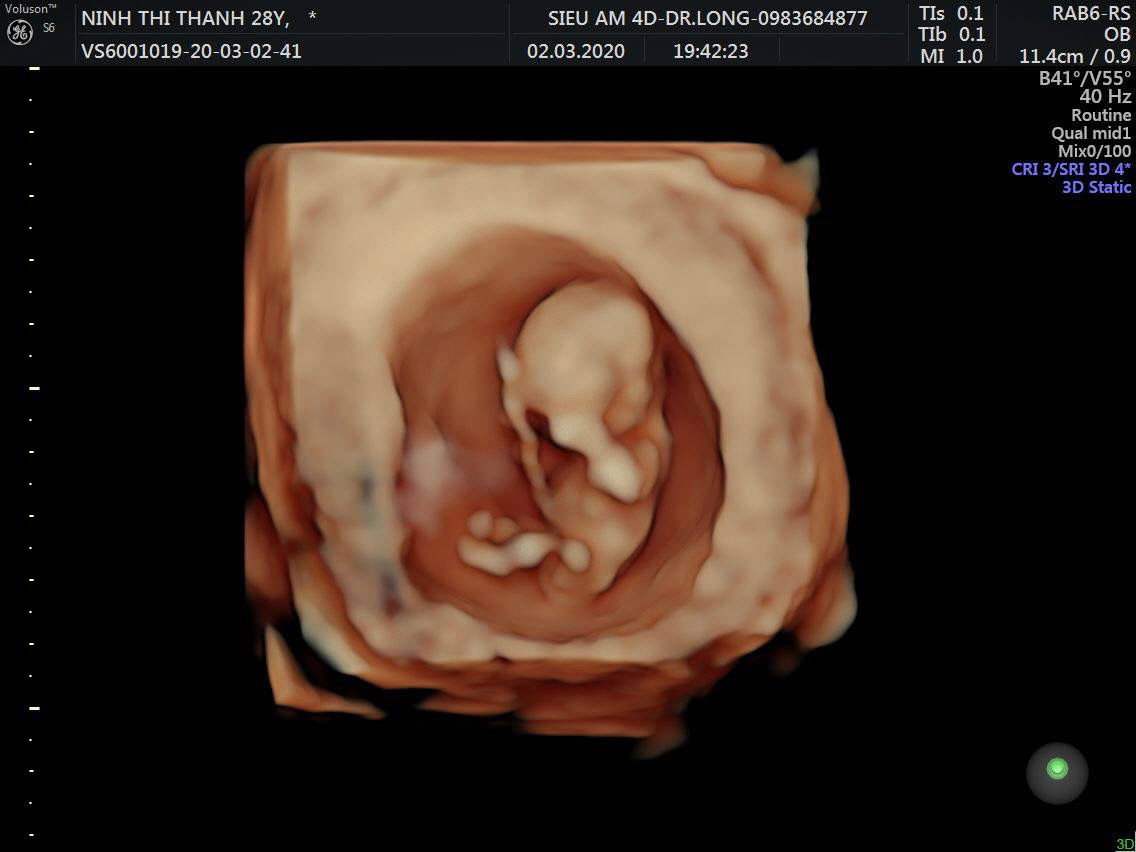

Thai 11w

Cho e hỏi Nhìn như này có biết trai hay gái ko mọi người